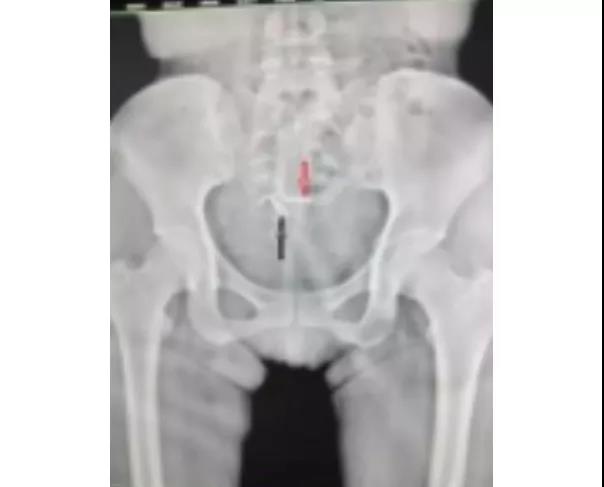

4、上环术后一月禁重体力劳动,以防环的脱落。来过一次月经后请来院复查环的位置是否正常。